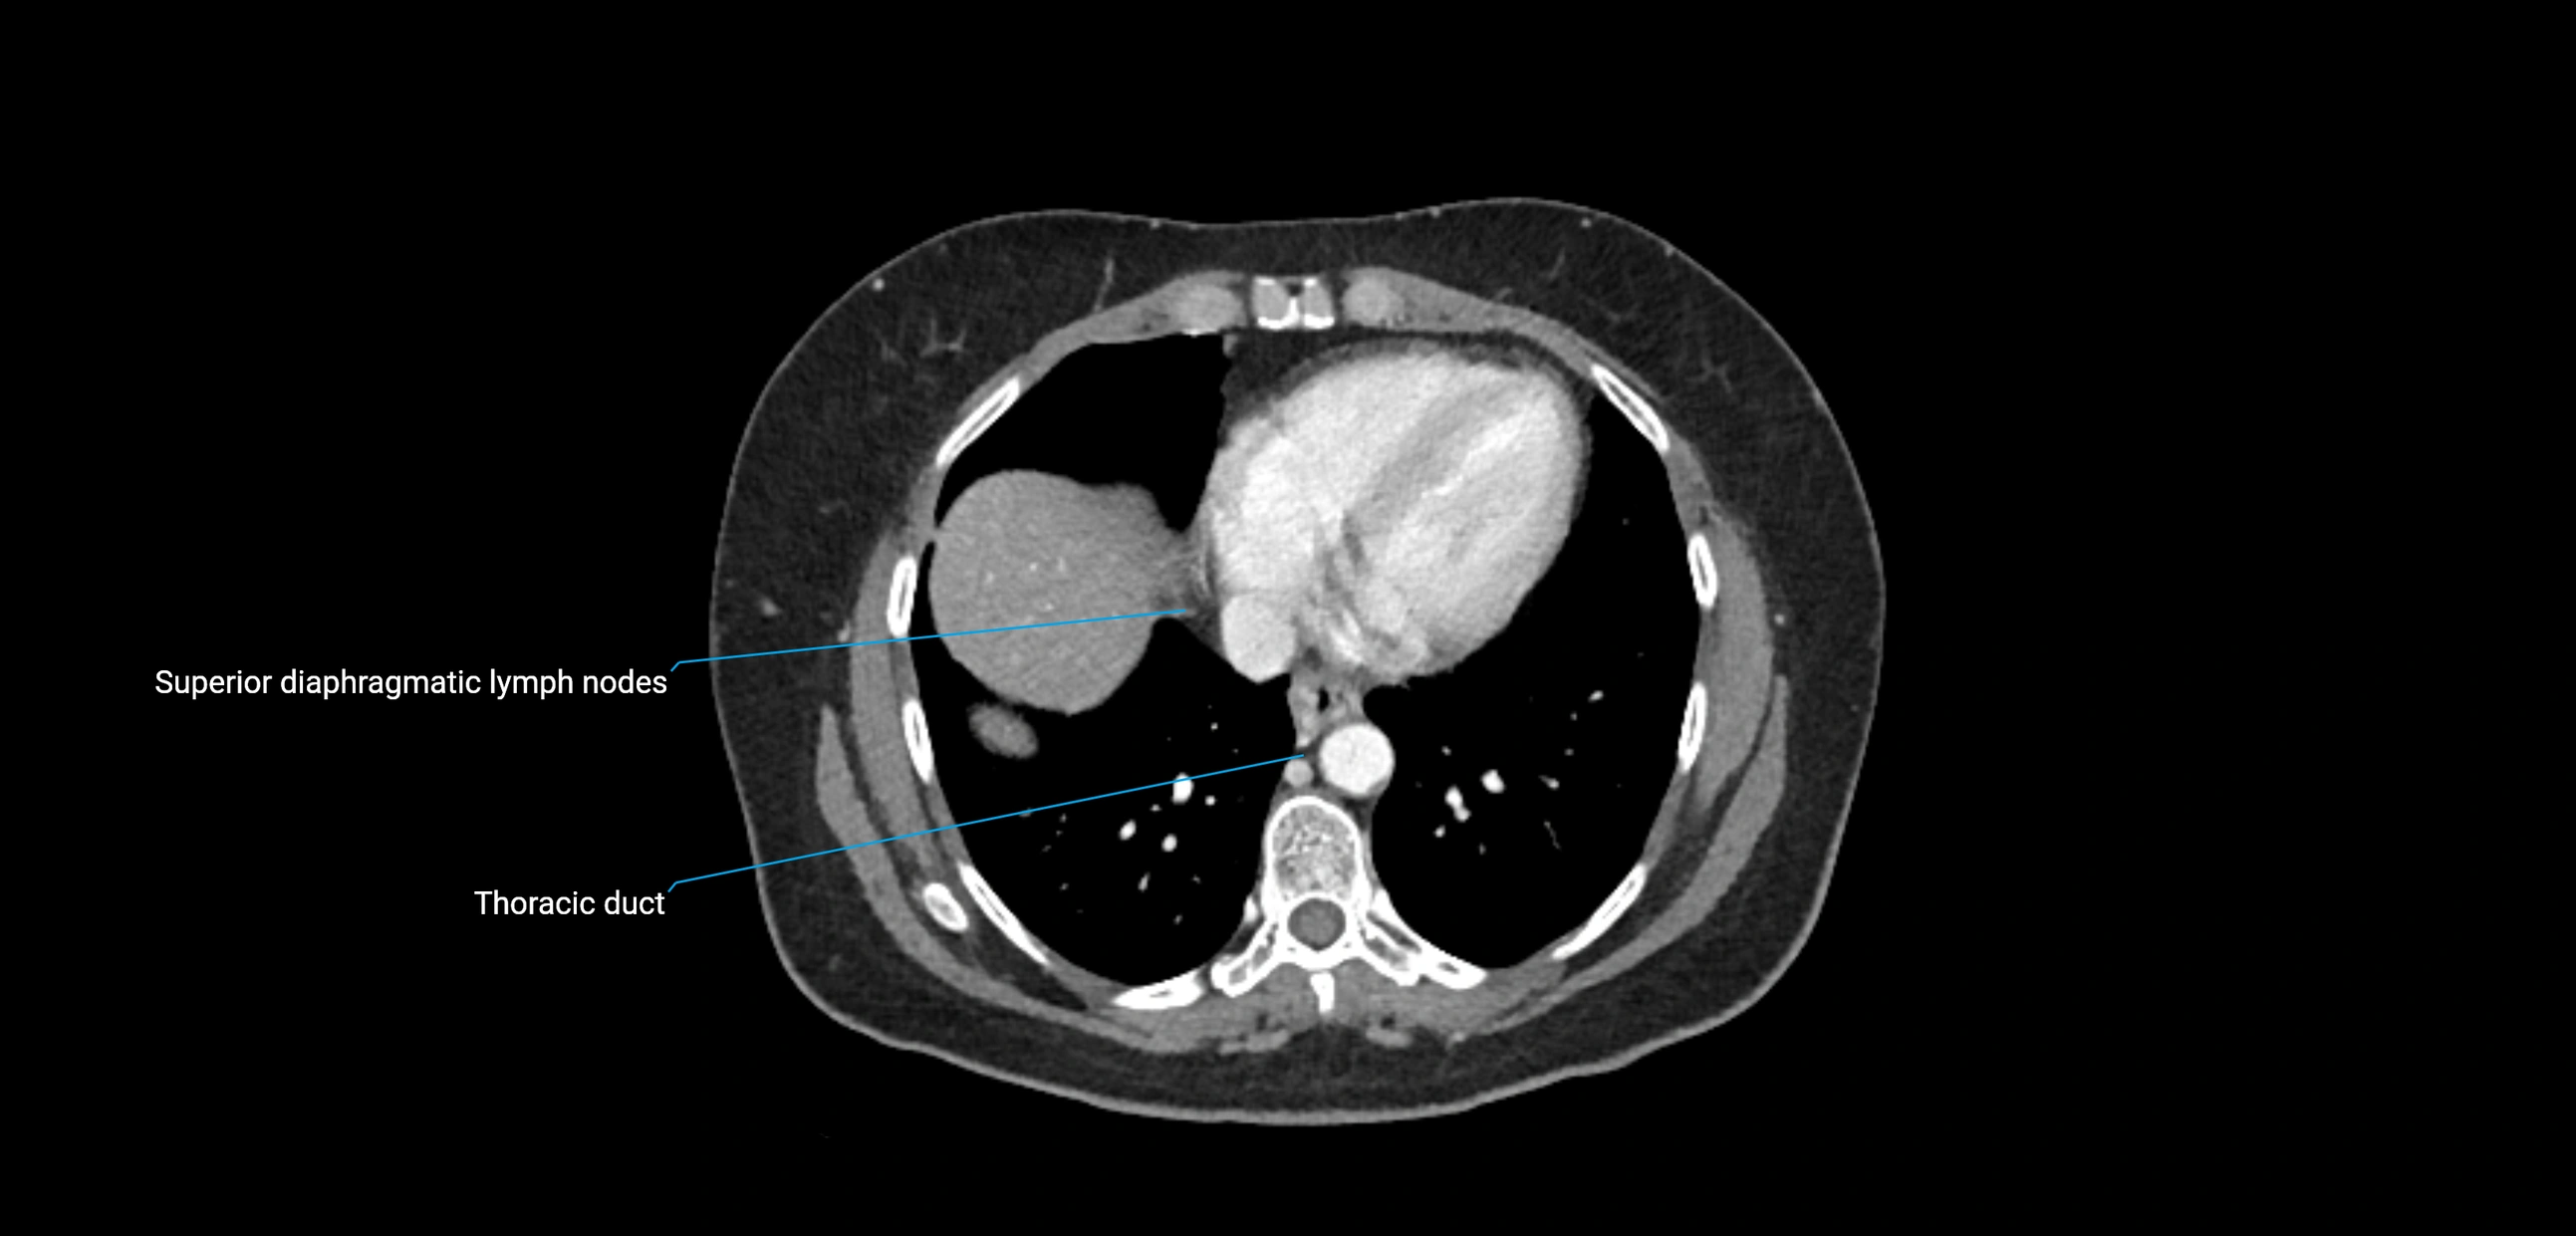

These nodes receive lymph from a wide range of abdominal and pelvic structures. Specifically, they drain lymph from the kidneys, suprarenal glands, gonads (testes/ovaries), uterus, uterine tubes, and pelvic organs, before converging into the lumbar lymphatic trunks, which terminate in the cisterna chyli → thoracic duct.

CT Appearance

CT Pre-Contrast:

• Nodes appear as soft-tissue density nodules adjacent to the aorta and IVC

• Calcification may be seen in chronic infections (e.g., tuberculosis)

CT Post-Contrast:

• Normal nodes enhance homogeneously

• Malignant nodes may show heterogeneous enhancement, central necrosis, or conglomerate formation

• Size >1 cm short axis is suspicious, though morphology and distribution are equally important

CT Venography (CTV):

• Demonstrates nodal encasement or compression of adjacent vessels (aorta, IVC, renal veins)

• Useful in staging testicular and ovarian malignancies

• Provides 3D reconstructions for retroperitoneal lymph node dissection planning